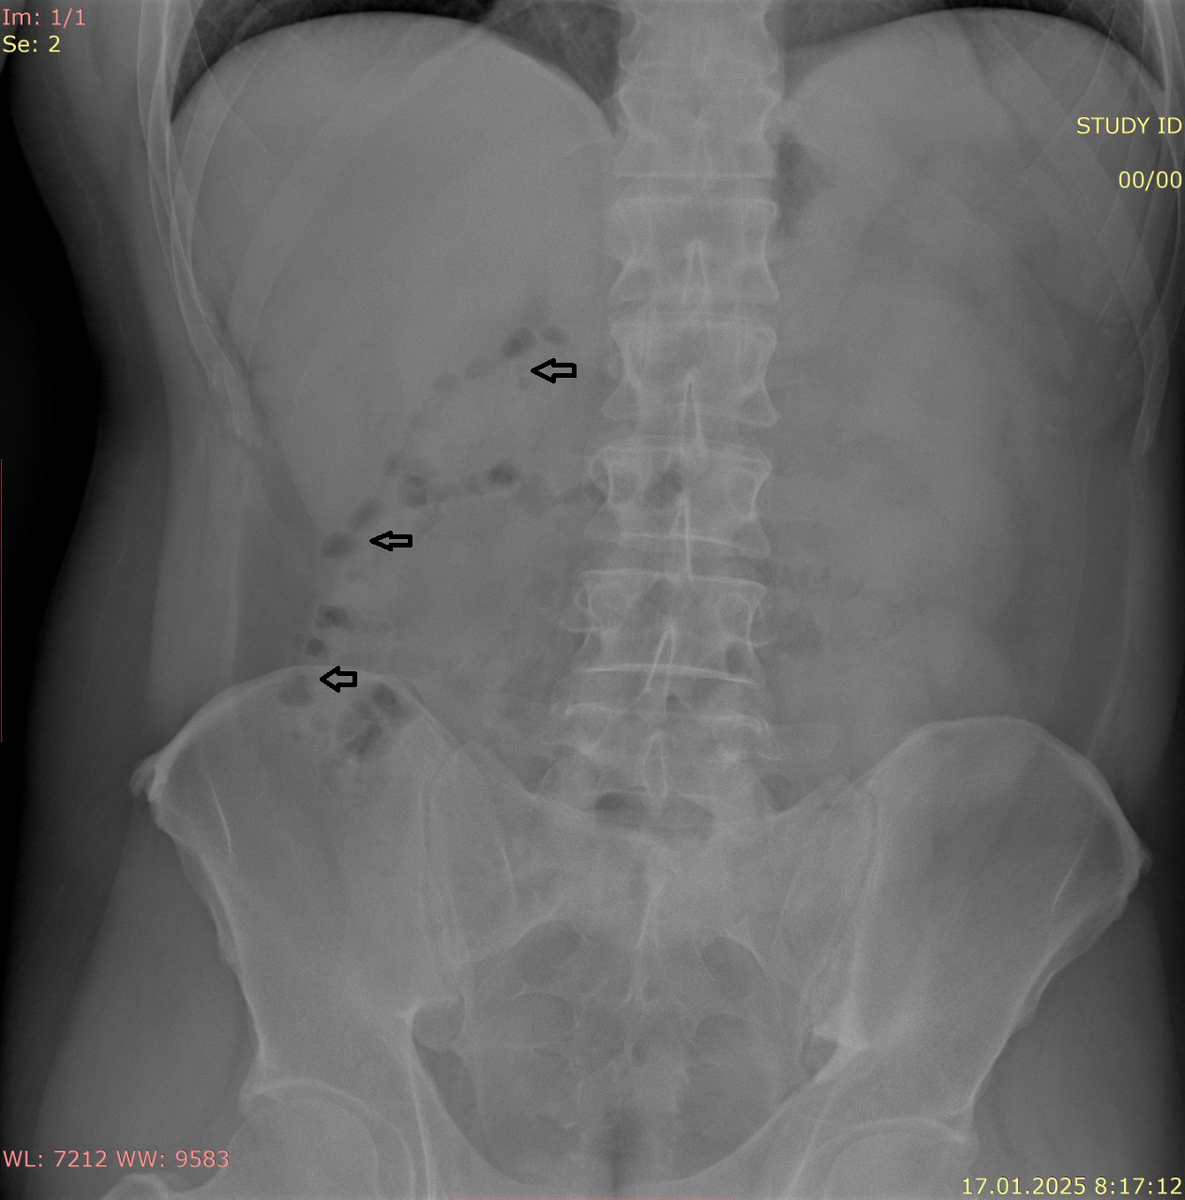

1. Тень кишечника: В норме на снимке живота можно видеть контуры тонкого и толстого кишечника. Тонкая петля кишечника обычно имеет диаметр менее 2,5 см, в то время как толстая петля может быть шире. Излишние или расширенные петли могут указывать на наличие кишечной непроходимости.

4. Почки: На рентгене могут быть видны тени почек, расположенные на задней стенке брюшной полости. Увеличенные или измененные по форме почки также могут указывать на патологии.

5. Костные структуры: Рентгенография позволяет визуализировать позвонки, ребра и таз. Любые изменения в их контуре или наличии фрагментов могут говорить о травмах или заболеваниях.

В правой верхней части могут быть видны печень и желчный пузырь, тогда как в левом верхнем квадранте располагается селезенка. Почки находятся на уровне L1 (верхний полюс), и на рентгеновских снимках они выглядят как парные тени. Важным аспектом является то, что на рентгеновских снимках также может быть видно количество свободного воздуха или жидкости, что может выявить наличие патологий в брюшной полости.